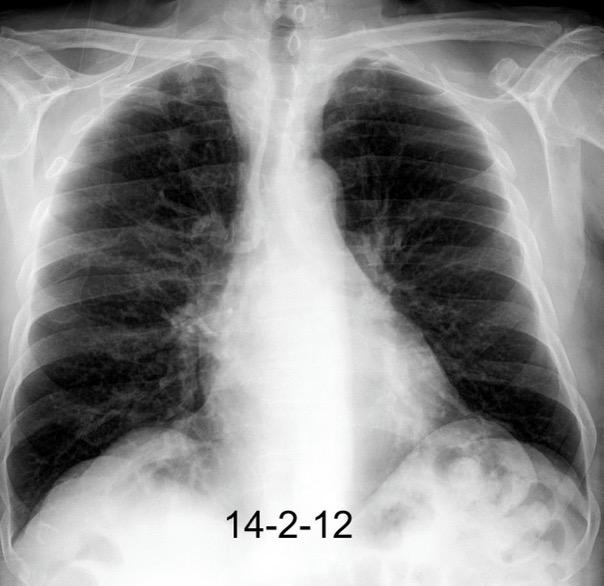

Triada de Garland

Ganglios paratraqueales derechos e hiliares bilaterales

95% de pacientes tienen ganglios hiliares bilaterales aislados o con afectación mediastínica (espec. paratraqueal derecho).

Criado E et al. Pulmonary sarcoidosis: typical and atypical manifestations at high-resolution CT with pathologic correlation. Radiographics. 2010